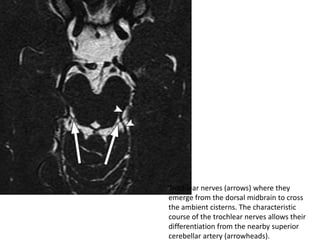

Trochlear nerves (arrows) where they

emerge from the dorsal midbrain to cross

the ambient cisterns. The characteristic

course of the trochlear nerves allows their

differentiation from the nearby superior

cerebellar artery (arrowheads).

Trochlear nerves (arrows)where they emerge from the dorsal midbrain to cross the ambient cisterns. The characteristic course of the trochlear nerves allows their differentiation from the nearby superior cerebellar artery (arrowheads).